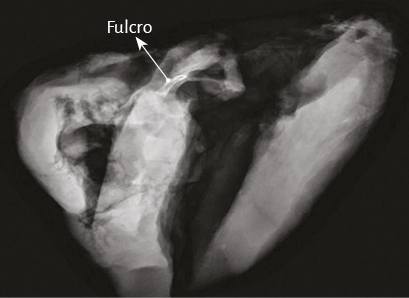

La existencia de una formación ósea, denominada os cordis, en bóvidos y ovejas es un hecho mencionado en ciencia veterinaria. Con posterioridad a nuestra primera publicación en 2018 sobre su hallazgo en el hombre (205), últimamente también fue ubicado en el chimpancé (109). En estas referencias es situada en el mismo sitio en el que nosotros hemos investigado esta estructura, tanto en bóvidos como humanos. Más allá de su mera alusión, hasta nuestras investigaciones nunca se le asignó ninguna función ni el sentido de su presencia, como asimismo careció de descripción en el ser humano (figuras 32 y 33) (216).

En bóvidos, la consistencia del fulcro cardíaco, óseo a la palpación (figuras 34 y 35), ha sido confirmada por la histología (figuras 36 a 38). Su tamaño, corroborado por disección (figura 39) y tomografía computada (figuras 58 y 59), es de aproximadamente 37 a 45 × 15 mm y de forma triangular. El análisis microscópico del fulcro cardíaco bovino muestra una matriz osteocondral trabecular con líneas segmentarias. Su estructura general asemeja al crecimiento metafisario de los huesos largos. A mayor aumento se pueden observar trabéculas óseas con osteoblastos y líneas segmentarias secundarias a aposición ósea. Los mismos hallazgos histológicos se han encontrado en chimpancés (109). La inserción secuencial de las fibras miocárdicas en el fulcro bovino se puede observar en las figuras 40-42.

Imágenes del fulcro cardíaco. Los corazones de bovino, estudiados con tomografía computada (figuras 58-60), resonancia magnética (figuras 61 y 62) y radiología simple (figura 63) evidenciaron el núcleo osteo-condroide hallado en la disección, observándose la misma morfología y tamaño análogo. En la tomografía humana hemos encontrado, en el análisis de la región donde se encuentra el fulcro cardíaco a través de las disecciones realizadas, la presencia de una intensidad en unidades Hounsfield por encima de 110 UH, mientras que el músculo adyacente tiene unidades por debajo de 80 UH. De esta manera, en la imagen, la estructura del fulcro alcanza un promedio de 132 ± 4,5 HU. En las áreas adyacentes, correspondiente al músculo miocárdico, este valor se ubicó entre 47,96 ± 12,5 y 77,59 ± 21,64 HU (figura 64).

Figura 63. Se observa fulcro cardíaco en imagen radiológica con técnica de mamografía en corazón bovino.